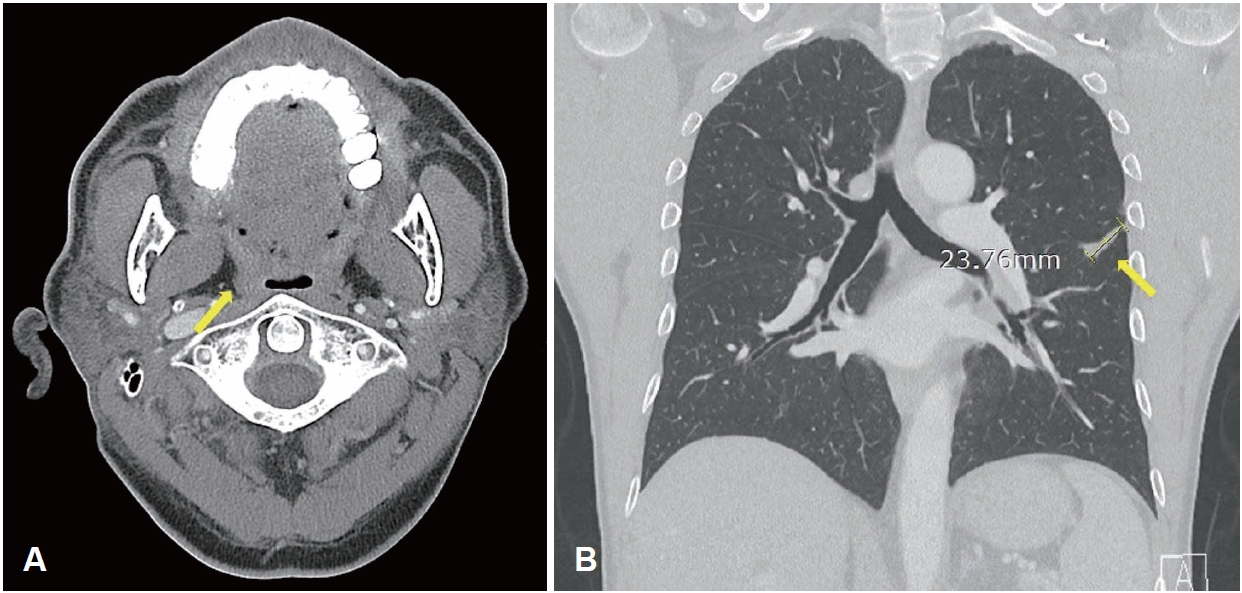

CaseA 54-year-old man presented to a local clinic with a 2-week history of throat foreign-body sensation and blood-tinged saliva. On physical examination, an oval ulcerative lesion was observed on the right tonsil, and biopsy suggested pleomorphic sarcoma or a poorly differentiated malignant tumor, and he was referred to the otolaryngology department of our hospital (Fig. 1). There was no history of alcohol use, and he had a smoking history of half a pack per day for more than 30 years. He had no notable medical history other than hyperlipidemia.

NotesAcknowledgments This case report was approved by the Institutional Review Board (IRB No.: EUMC 2025-09-061). Author Contribution Conceptualization: Han Su Kim. Data curation: Eun Bin Lee. Investigation: Eun Bin Lee. Methodology: Han Su Kim. Project administration: Eun Bin Lee. Resources: Han Su Kim. Supervision: Han Su Kim. Validation: Han Su Kim. Writing—original draft: Eun Bin Lee. Writing—review & editing: Han Su Kim. Fig. 1.Endoscopic view at the initial outpatient evaluation showing an ulcerative, protruding mass in the right palatine tonsil. Fig. 2.Radiologic findings. A: Contrast-enhanced neck CT showing a 1.8-cm peripherally enhancing, centrally low-density lesion in the right palatine tonsil (yellow arrow). B: Neck MRI showing a 2.3-cm lobulated mass in the right palatine (yellow arrow) tonsil with intermediate T2 signal intensity. C: Chest CT showing a 3.8-cm lobulated mass (yellow arrow) extending across the left major fissure and involving the adjacent pleura. D: PET-CT demonstrating fluorodeoxyglucose uptake in the right palatine tonsil (yellow arrow, SUVmax 21.64), left lower lobe lung lesion (blue arrow, SUVmax 26.41), left hilar lymph node (blue arrow, SUVmax 29.64), and small intestine (green arrow, SUVmax 16.55). Fig. 3.Pathologic findings from the right palatine tonsil biopsy. A: Hematoxylin-eosin–stained specimen showing poorly differentiated carcinoma, favoring metastatic non-small cell lung carcinoma (original magnification ×100). B: Immunohistochemical specimen showing diffuse positivity for cytokeratin pan (CK-PAN), supporting epithelial origin (original magnification ×100). C: Immunohistochemical staining for P40 showing negative results, arguing against a primary squamous cell carcinoma of the tonsil (original magnification ×100). D: Immunohistochemical specimen showing focal vimentin expression, which can be observed in poorly differentiated carcinomas with partial mesenchymal features (original magnification ×100). Fig. 4.Post-treatment radiologic assessment following CCRT. A: Follow-up neck CT showing no residual enhancing mass in the right palatine tonsil (yellow arrow). B: Follow-up chest CT showing a decreased size of the previously noted lobulated mass (yellow arrow) extending across the left major f issure. REFERENCES1. Unsal M, Kutlar G, Sullu Y, Yurtlu S. Tonsillar metastasis of small cell lung carcinoma. Clin Respir J 2016;10(6):681-3.